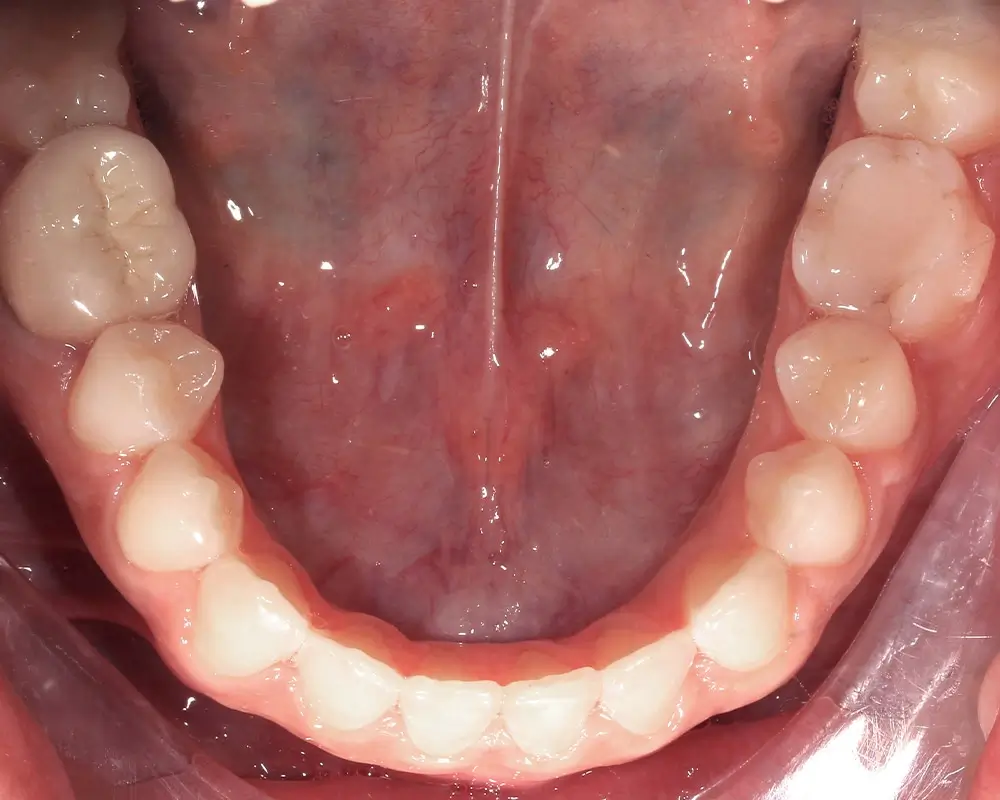

Открытый прикус - Кейс 5

Эффективность устранения дефекта прикуса посредством элайнеров FlexiLigner.

Результаты лечения